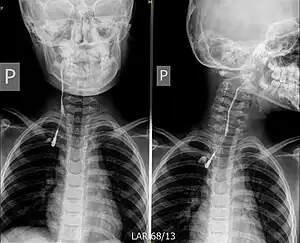

Fistulogram (sinogram) of a right branchial cleft sinus.